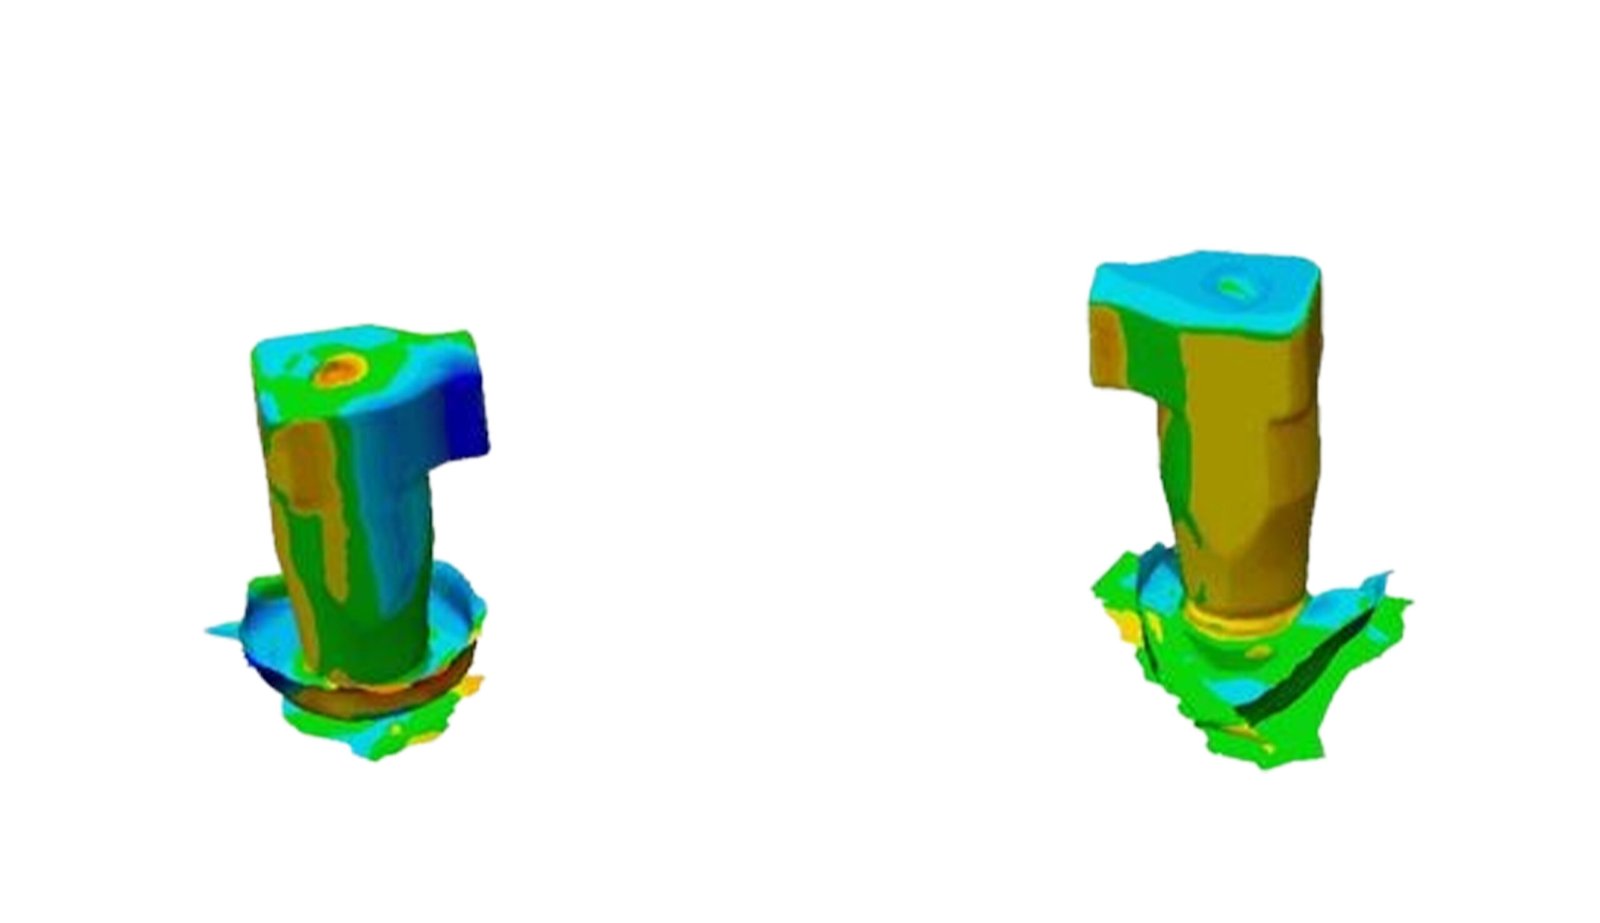

This section specializes in high-precision 3D deviation mapping to compare pre- and post-treatment anatomical or implant-related geometries. Using advanced superimposition and deviation algorithms, we quantify micro-level shifts, deformation zones, and structural discrepancies with sub-millimeter accuracy. These analyses support quality control, surgical verification, and design validation. The resulting deviation heat-maps provide clear, data-driven insights that enhance clinical decision-making and device optimization.